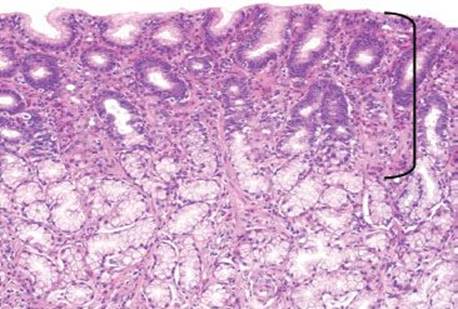

Figure 2.153 Gastric mucosal eosinophilia pattern, peripheral eosinophilia. At scanning magnification, one can appreciate the expanded lamina propria with an eosinophilic hue in this antral biopsy (bracket). This patient is known to have peripheral eosinophilia and increased eosinophils in the small bowel and colon, as well, with an established diagnosis of idiopathic eosinophilic gastroenteritis.